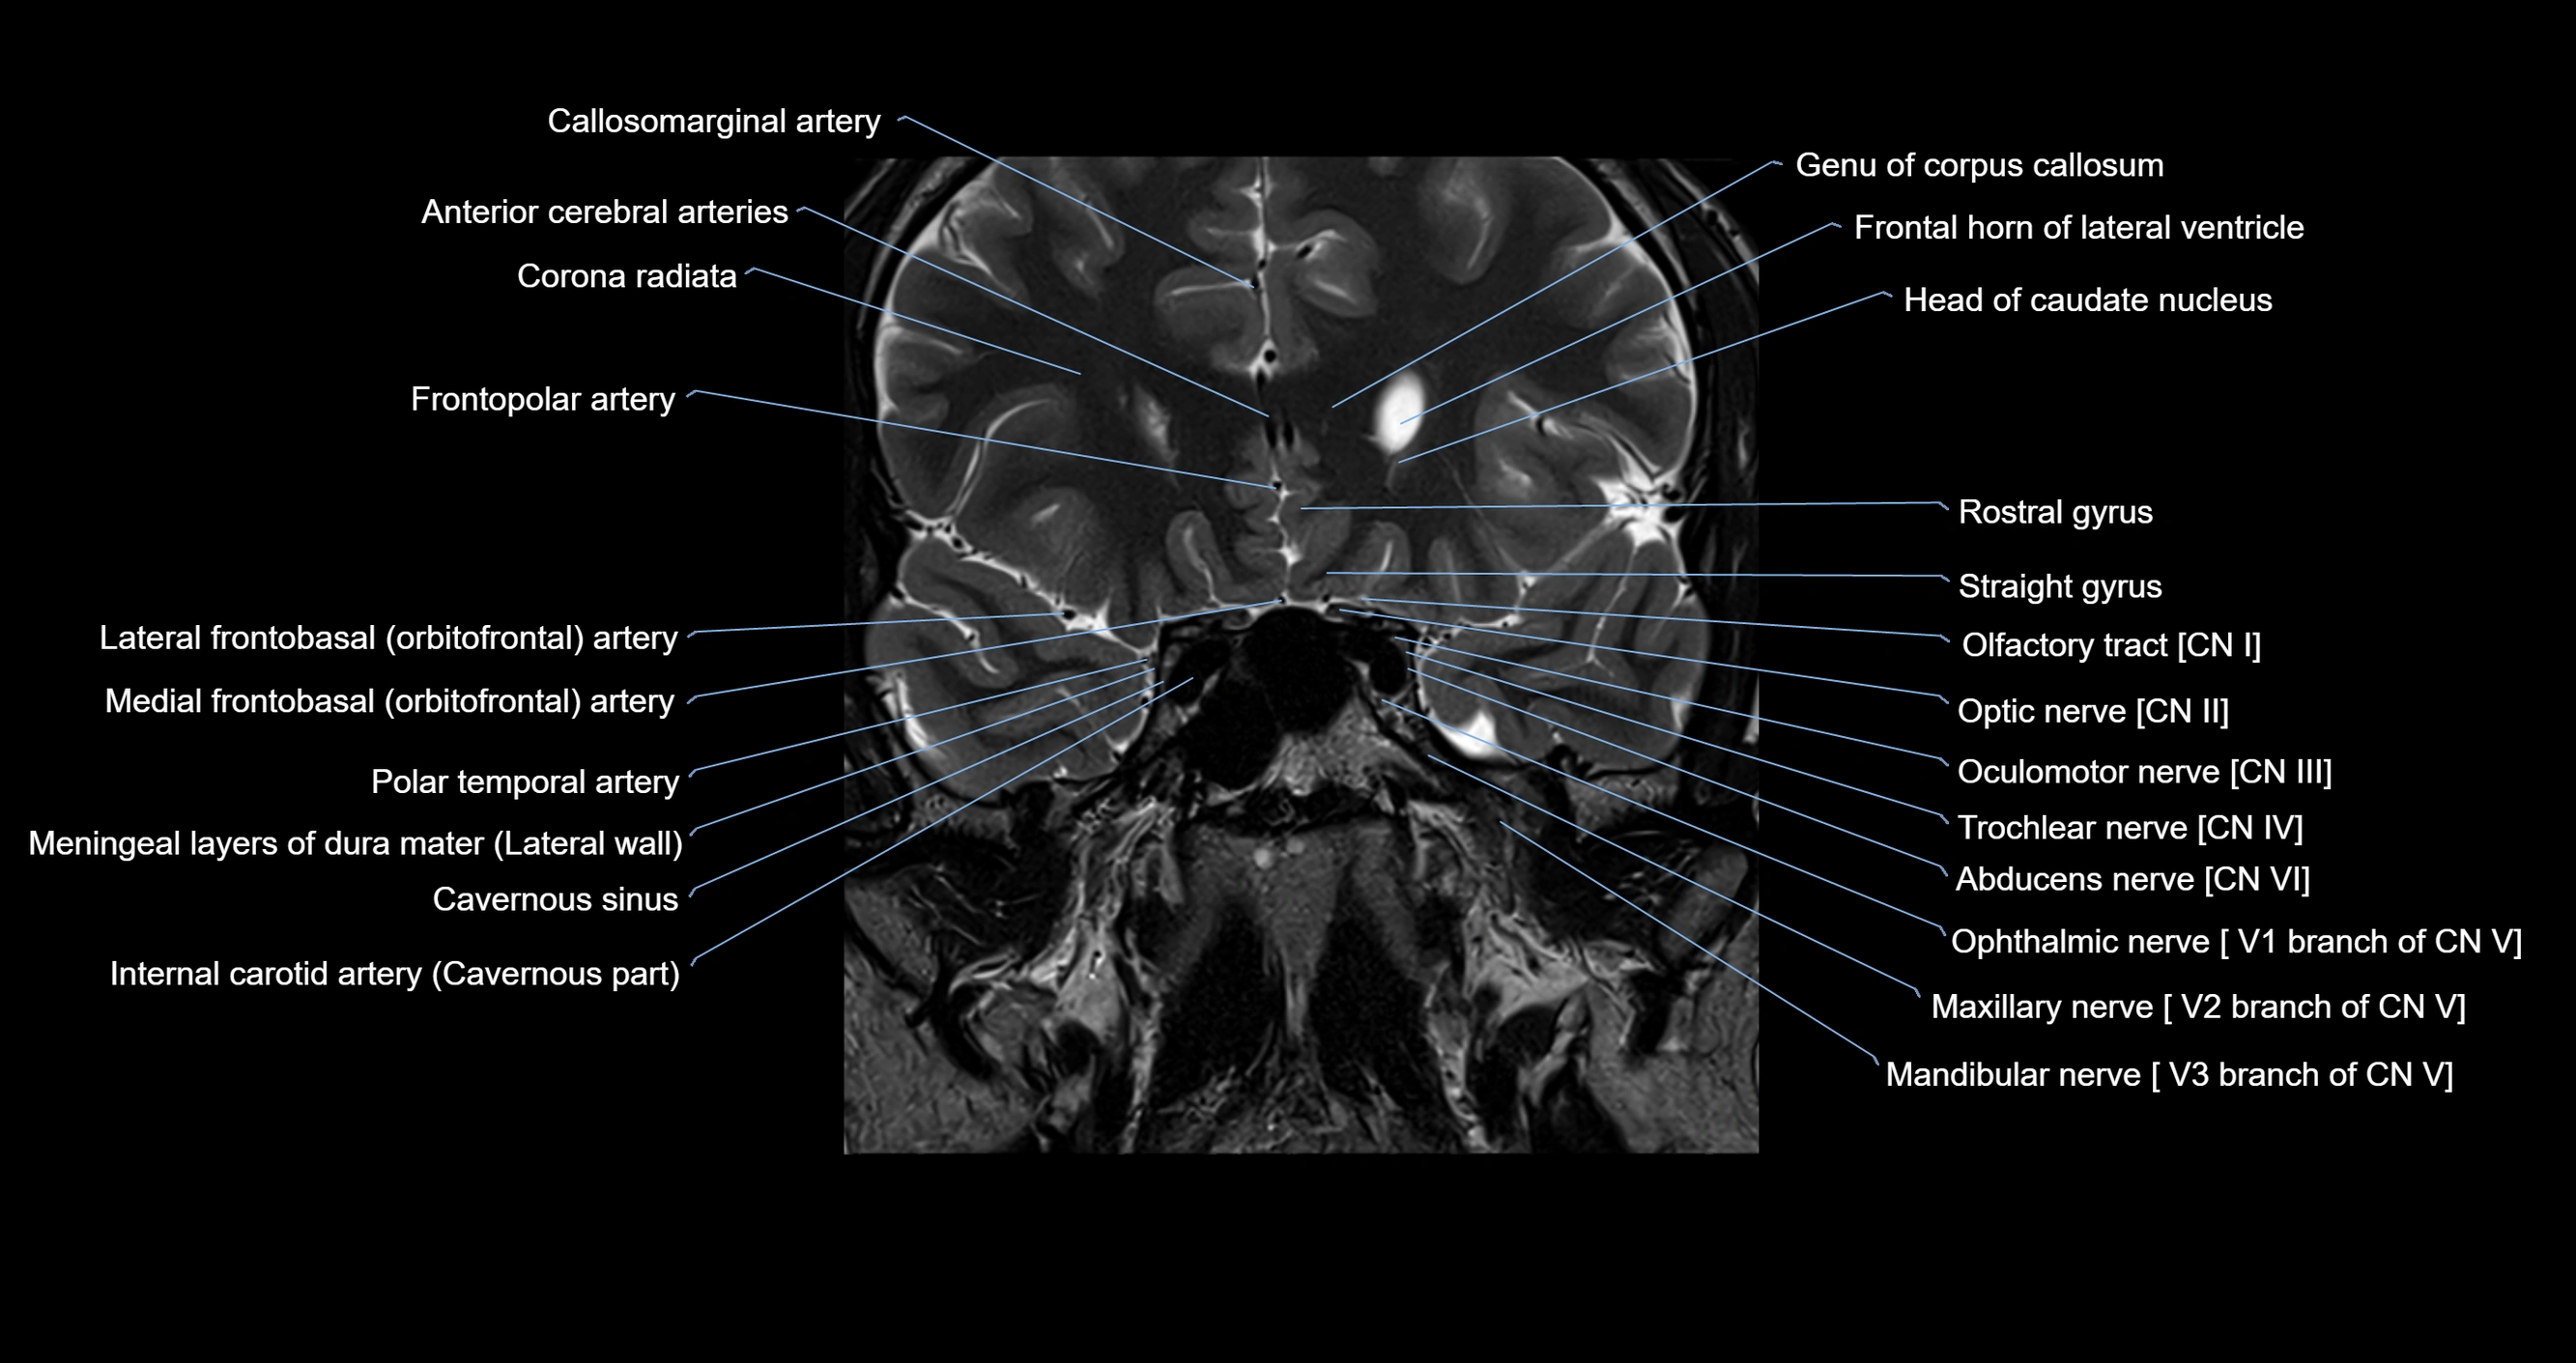

MRI images